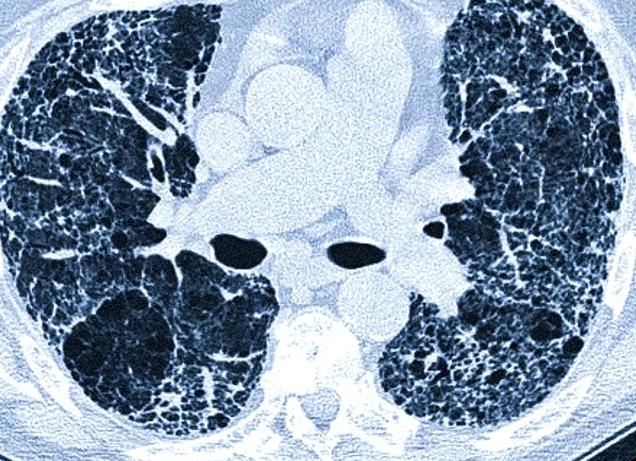

Компьютерная томография (КТ) – современный информативный метод послойного исследования внутренних органов и тканей человека. КТ основана на просвечивании тела рентгеновскими лучами, фиксации и обработке компьютером разности ослабления излучения при прохождении через различные ткани организма. Метод предусматривает создание послойных снимков, имитирующих «разрез» тела с небольшим шагом в разных проекциях. Диагностическая ценность томографии – очень велика: она позволяет увидеть расположение органов, их размеры, локализацию, патологии и новообразования, получить их характеристику.

- КТ легких выполняют для визуализации бронхов, сосудов, средостения и выявления различных патологий.